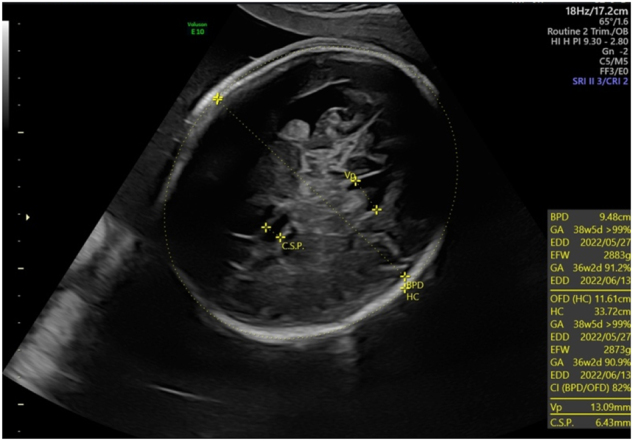

Case presentation: It is the case of prenatally diagnosed cDM. In 32 weeks of pregnancy multiple sonographic findings such as severe polyhydramnios, bilateral talipes, fetal legs akinesia, macrocephaly with mild bilateral ventriculomegaly, right-sided pleural effusion and diaphragmatic pathology were observed by fetal medicine specialist. As the patient complained of weakness in her limbs, she was consulted by a neurologist. The neurological examination revealed a pathognomonic sign of DM1 - grip myotonia. The amniotic fluid and the mother's blood sample were further tested for DM1. This identified >150 repeats in one copy of the DMPK gene of the both, which is consistent with the diagnosis DM1.